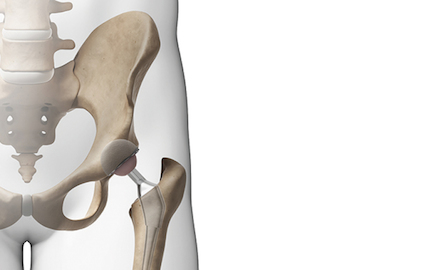

It is vital during total hip replacement surgery that the implant hardware is aligned correctly to limit the possibility of later complications. Every patient has a unique pelvic motion and Optimized Ortho developed dynamic modelling technology which provides pre-surgical information on the patient’s predicted biomechanics.

Optimized Ortho engaged Park Industrial to enable the second stage of their implant positioning system. We created surgical guides uniquely shaped to match the pelvis of each patient that were derived from X-ray and CT scan data. These guides are then fabricated from the latest 3D printing techniques using biocompatible materials.